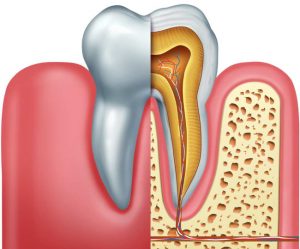

Although a dentist will always strive to do everything they can to help you keep all of your teeth, there are dozens of reasons you may need to have...